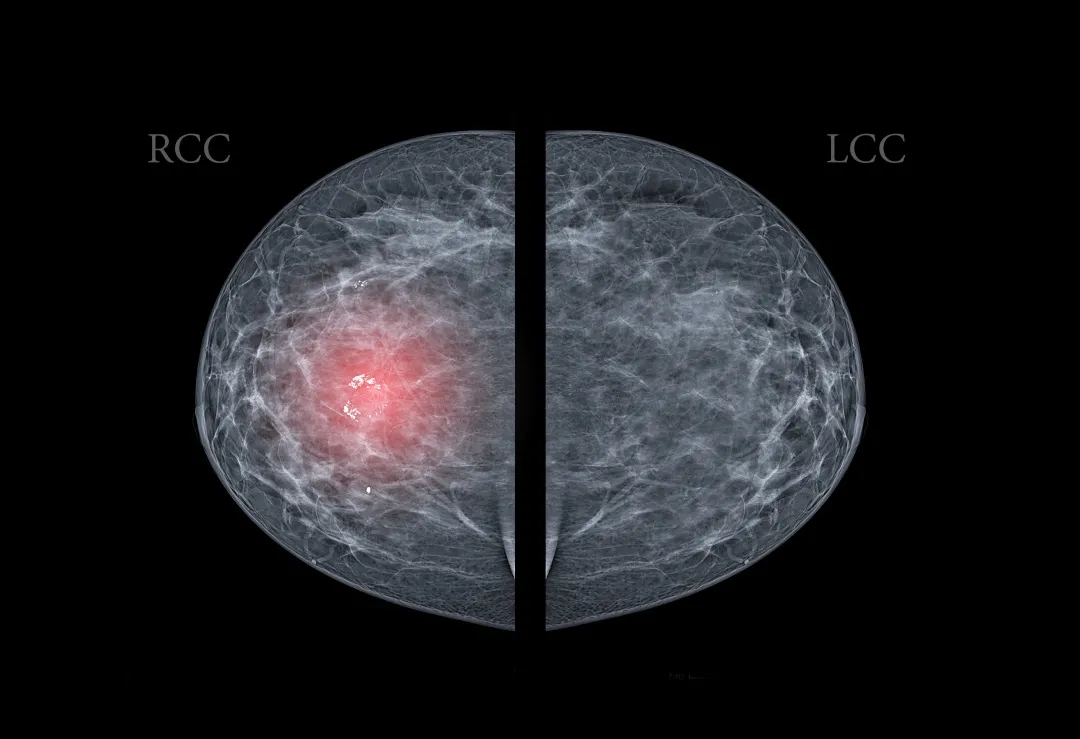

如何評判乳腺結(jié)節(jié)的惡變概率呢?其實(shí)我們可以通過一項(xiàng)報(bào)告來觀察乳腺結(jié)節(jié)惡變的風(fēng)險(xiǎn)等級:BI-RADS[3]。

BI-RADS是評價(jià)乳腺結(jié)節(jié)良性、惡性的統(tǒng)一分級標(biāo)準(zhǔn),分為5個(gè)等級,用0~5進(jìn)行表示,級數(shù)越高,惡性程度越高。

溫馨提示:

當(dāng)診斷結(jié)果在BI-RADS-4類以上,考慮有較高的惡變幾率,應(yīng)盡快前往乳腺外科就診,請醫(yī)生進(jìn)行詳細(xì)評估。